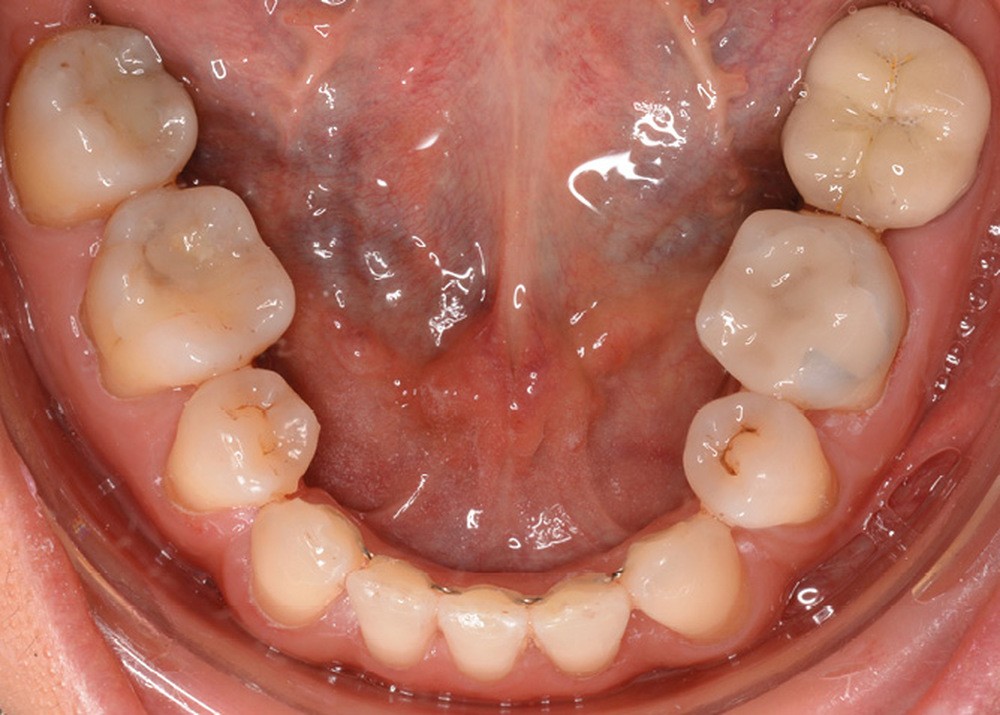

Sur le plan dentaire, la patiente est en classe III droite et gauche, canine et molaire de 6 mm, avec une occlusion inversée antérieure localisée à 11, 12 et 22. Elle présente une dysharmonie dents-arcades sévère, une agénésie d’une incisive mandibulaire est à signaler, et les troisièmes molaires ont été extraites à l’âge de 21 ans.

Au niveau fonctionnel, on note un bruxisme statique avec contact permanent entre les dents maxillaires et mandibulaires. La patiente présente des prématurités en relation centrée sur les incisives, le guidage en propulsion est perturbé et des interférences multiples sont retrouvées en latéralités droite et gauche.